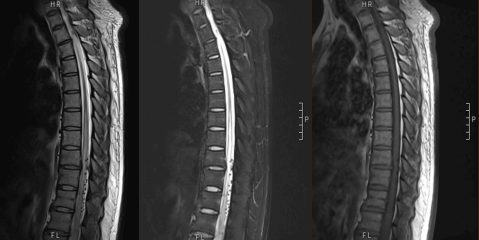

病例3

患者81岁,男。 突发腰背部疼痛伴排尿困难18d、双下肢麻木无力1d。

答案:脊髓血管畸形-硬脊膜动静脉瘘。解析同上。